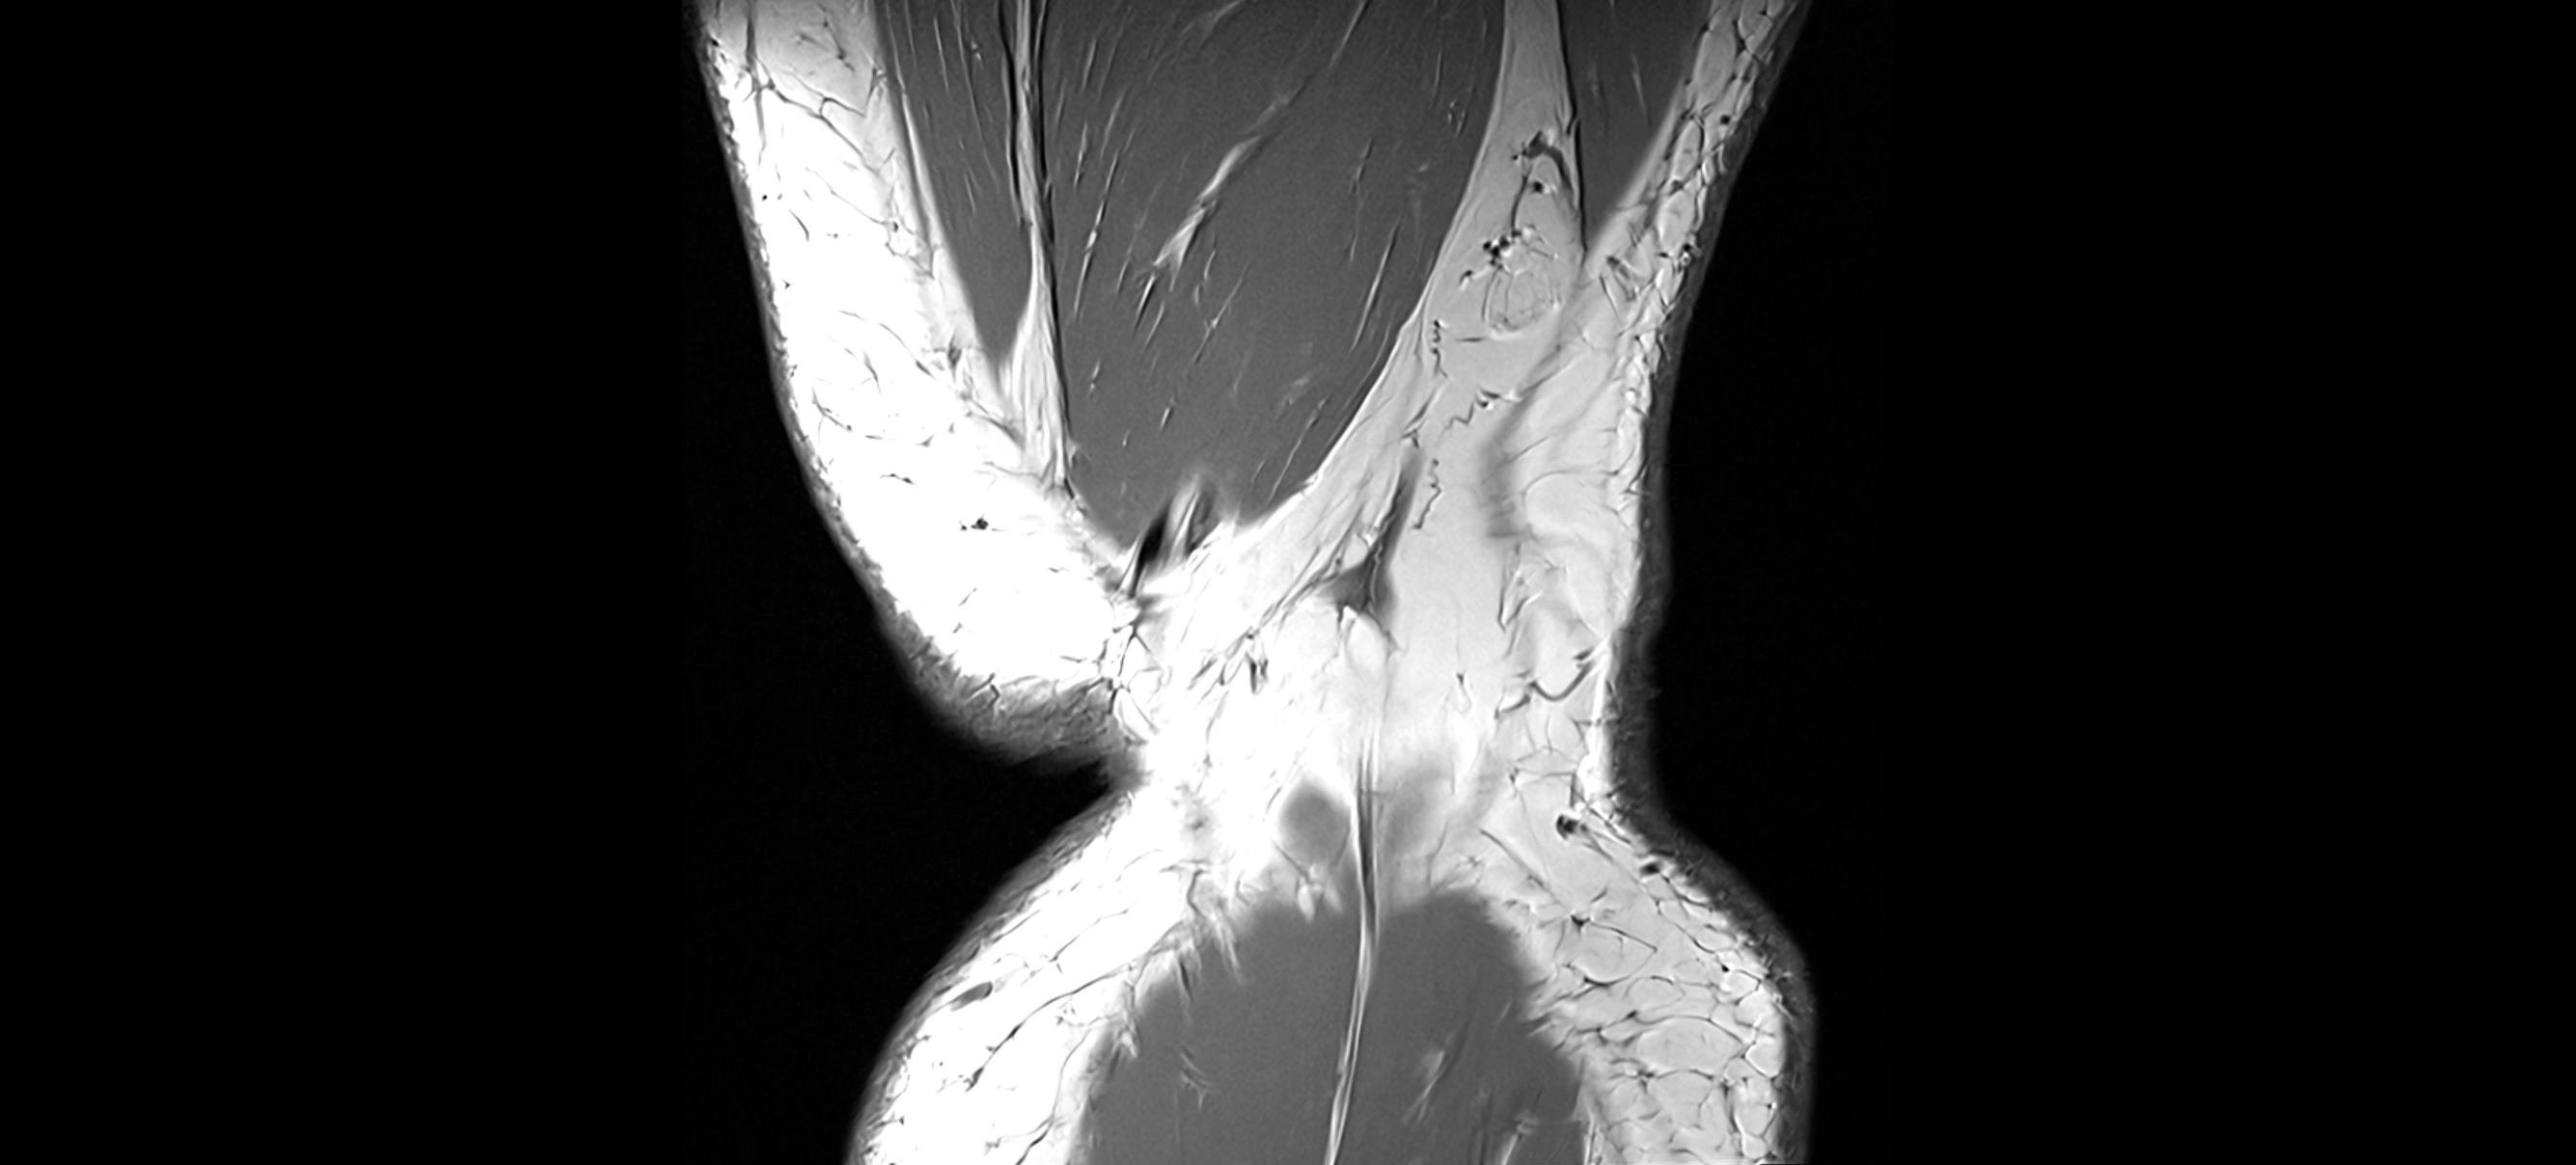

T2-weighted images:

• Normal ACL remains low signal

• Partial or complete tears appear as discontinuity, increased signal, or fiber laxity

STIR (Short Tau Inversion Recovery):

• Normal ACL shows dark low signal

• Acute injury shows bright hyperintensity due to edema and hemorrhage

Proton Density Fat-Saturated (PD FS):

• Normal ACL: dark, low-signal band

• Tears: bright intraligamentous hyperintensity, discontinuity, or abnormal course